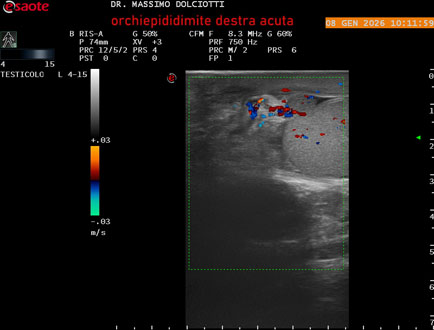

Data inserimento: 08/01/2026

Ecografia del: 08/01/2026

Strumento: Esaote MyLab Eight

Sonda: Lineare Multifrequenza 4-15 MHz

Età Paziente: M 74 anni

Motivazione dell'esame: da 3 giorni dolore e tumefazione al testicolo destro.

Commento all'esame: le immagini ed il video documentano il didimo destro, aumentato di volume, con incremento della vascolarizzazione; aumentato di volume e di vascolarizzazione anche l'epididimo destro, Normale il didimo sin e l'epididimo sinistro, Gli elementi ecografici segnalati orientano per orchiepididimite destra acuta.

Conclusioni: orchiepididimite destra acuta (right acute orchiepididymitis).

Presentazione: Dr. Massimo Dolciotti - Ancona